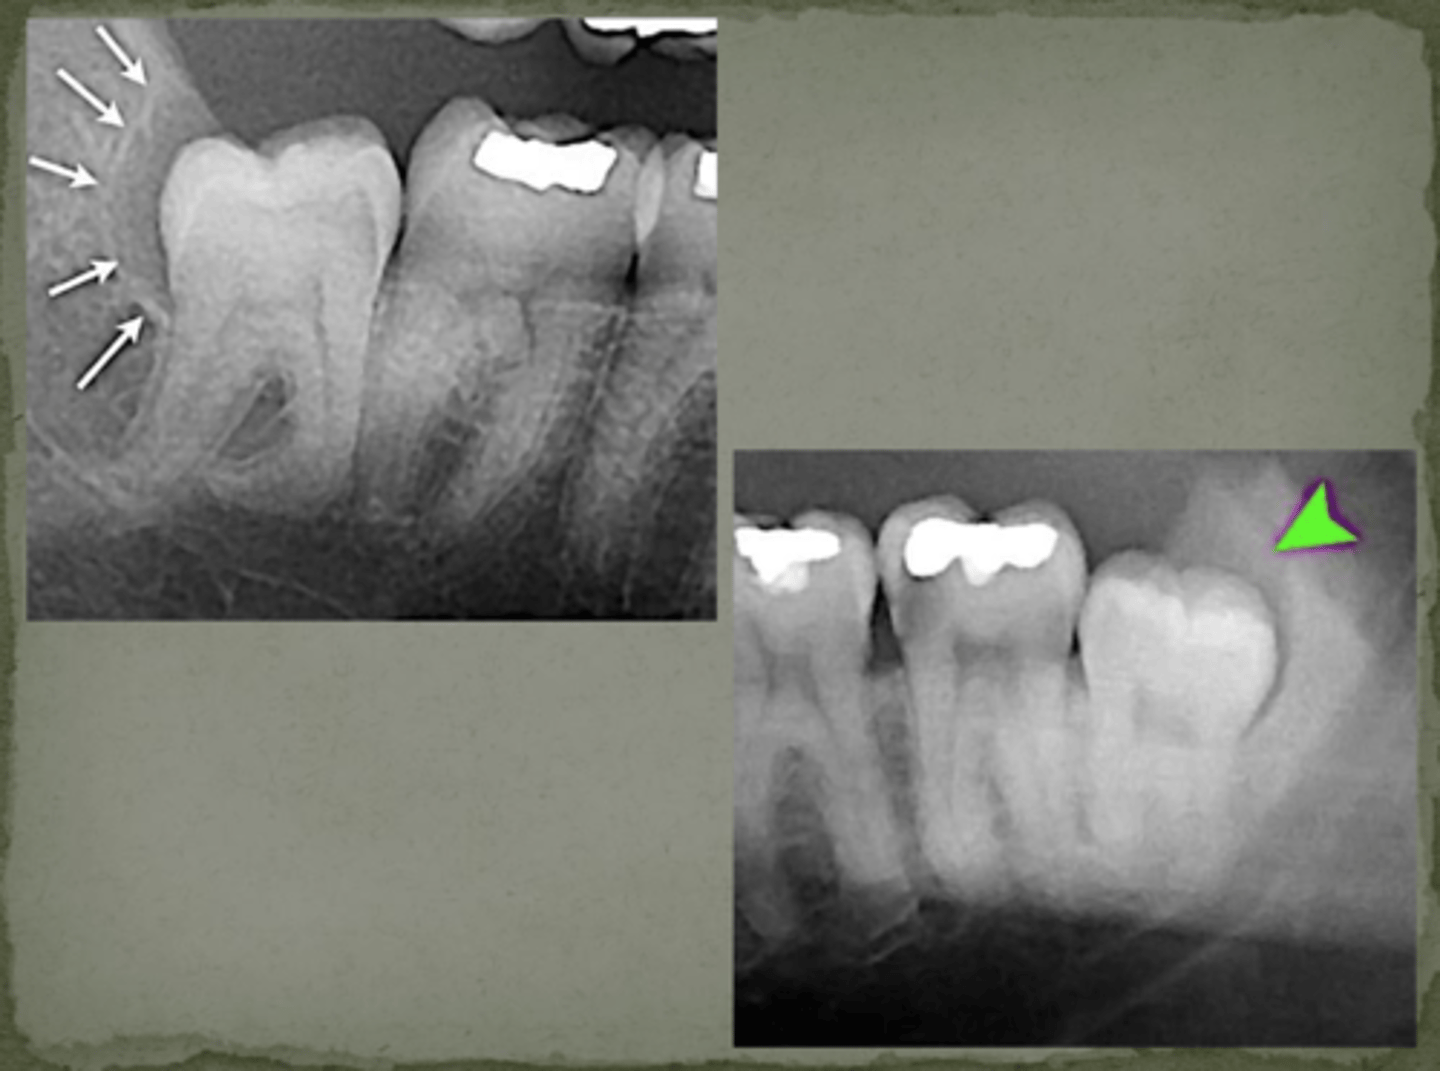

What indicates osteomyelitis if borders are irregular?

Choose osteomyelitis

What is sequestration in chronic osteomyelitis?

Necrotic bony islands

What develops during chronic osteomyelitis?

Sinus tract